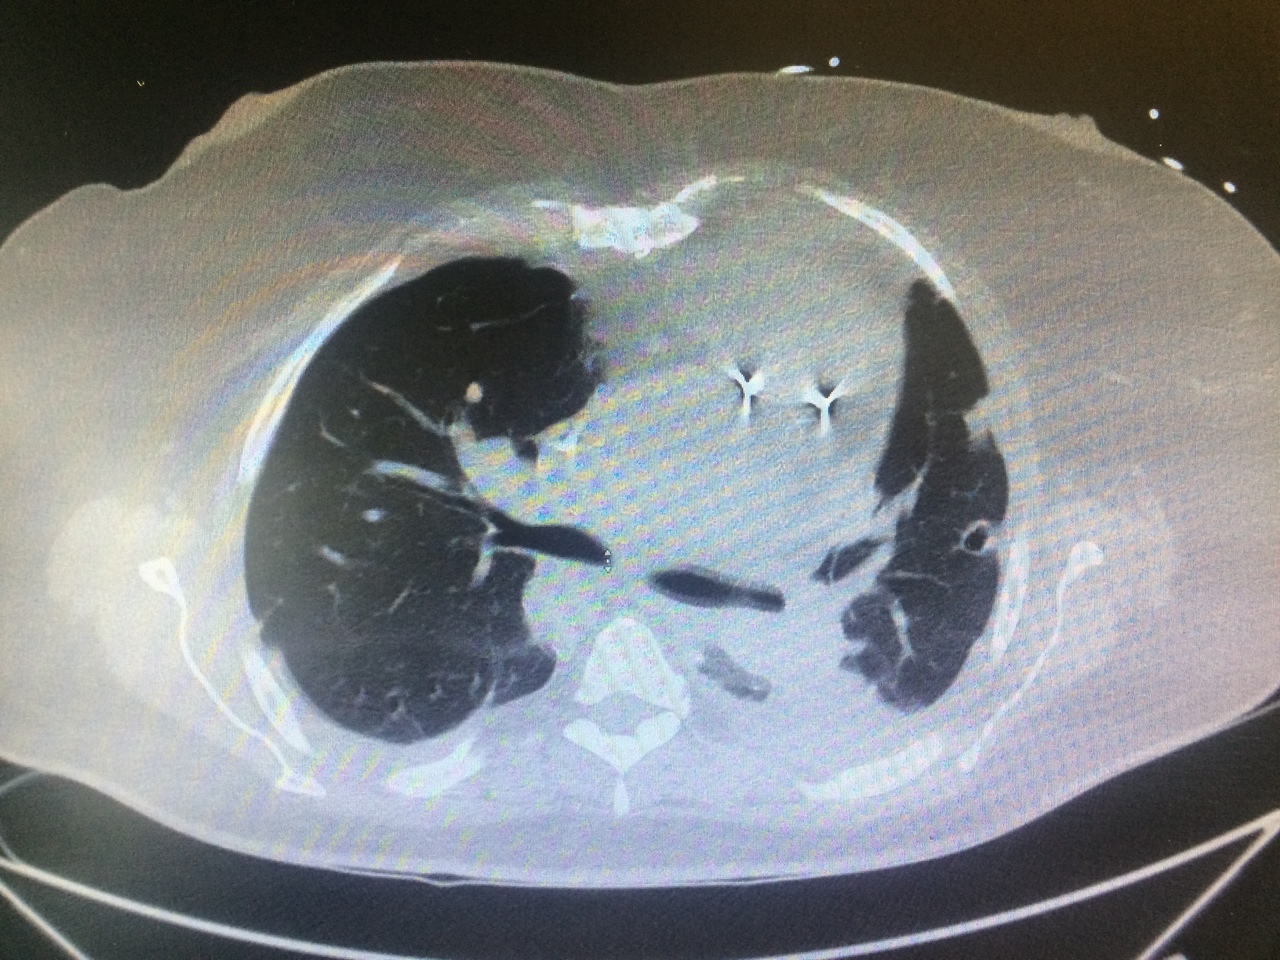

Voici les images du scanner thoracique.

Question 11 : Quelle est votre suspicion diagnostique ?

Syndrome septique chez un porteur de valve prothétique pulmonaire, examen direct suggérant un sepsis à staphylocoques (germe pourvoyeur d’EI), nombreux emboles pulmonaires excavés